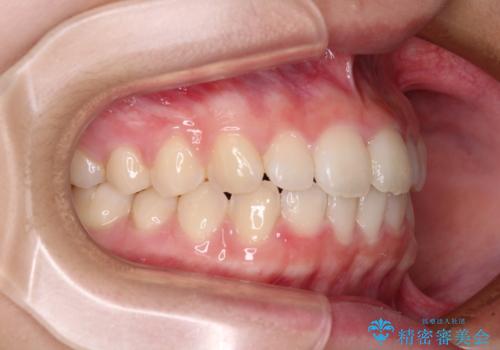

- 前歯のデコボコを気にして来院された高校生の患者様です。

捻れた前歯が前方に飛び出している点も気になっており、目立たない装置を希望されたため、インビザラインを用いて矯正治療を行うこととしました。

上下ともに少し捻れが残っていたため、治療の継続を提案しましたが、本人も親御さんも満足とのことで、治療を終えました。

捻れの改善により突出感も改善されました。